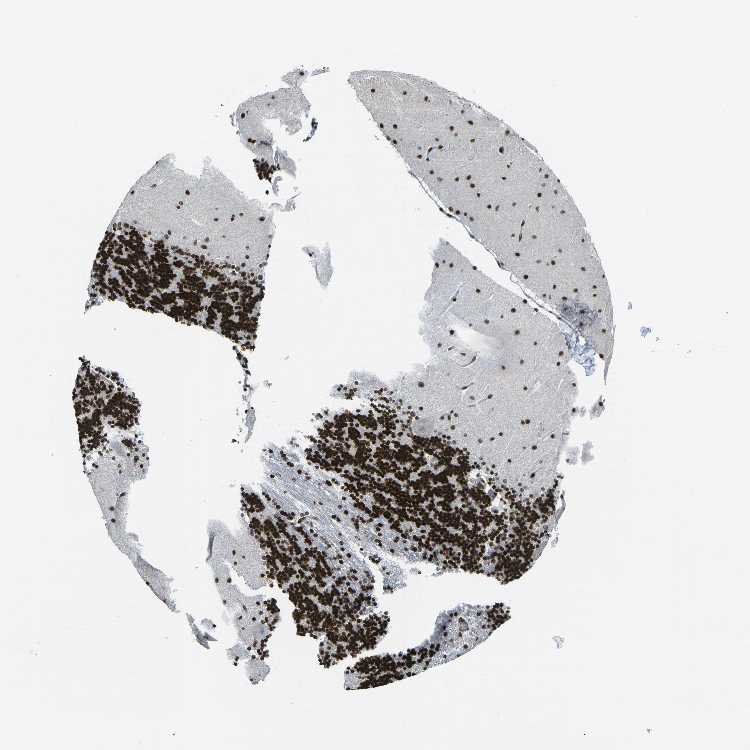

CEREBELLUM - Antibody stainingi

Antibody staining in the annotated cell types in the current human tissue is reported as not detected, low, medium, or high, based on conventional immunohistochemistry profiling in selected tissues. This score is based on the combination of the staining intensity and fraction of stained cells.

Each image is clickable and will lead to virtual microscopy that enables deeper exploration of all samples and also displays staining intensity scores, fraction scores and subcellular localization as well as patient and tissue information for each sample.

Antibody HPA068431Antibody CAB012235

Cells in granular layer High-

Cells in molecular layer High-